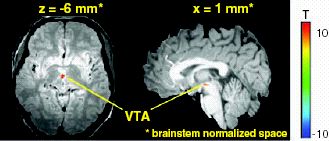

Ventral tegmentales ArealEine Hirnregion, die von Fachärzten, Hirnforschern und Kennern der Materie – wegen ihrer Lage im bauchwärts (anat.: ventral) liegenden Bereich des Hirnstamms – ventral tegmentales Areal (VTA) genannt wird. Sie ist das A und Ω und der Ursprungsort des Lust-, Belohnungs- und Glückssystems. Im VTA beginnt und endet es nach Rückmeldungen von Partnerzellen im Mittel- und Vorderhirn:

Zwei funktionelle Magnetresonanz-Tomografie-Aufnahmen vom VTA, © Kimberlee D'Ardenne, Science, 2008

Aktive VTA Dopamin-Nervenzellen von hinten